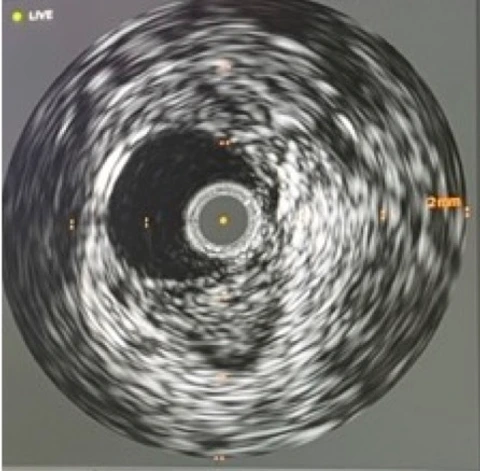

Querschnitt Posterior Tibial Arterie

The Applied Vascular Research Group aims to truly explore mechanisms of arterial and venous vascular disease by integrating molecular research, large animal models, first-in-man studies and multicenter clinical trials. One core research focus is to tackle restenosis, the Achilles heel of peripheral vascular interventions, by identifying patients at risk and developing improved treatment options. As peripheral arterial disease contributes to significant morbidity and mortality and is still severely understudied, there is an urgent need to improve both routine patient care as well as our knowledge on the mechanisms and outcomes of the disease.